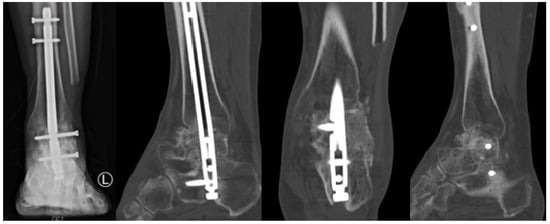

Postoperatively, patients were immobilized in a non-weight-bearing cast for 4 weeks to ensure initial stabilization and healing. Following this initial immobilization period, patients were transitioned to wearing controlled ankle motion boots for an additional 4 weeks to maintain non-weight-bearing status. After the total 8-week period of non-weight-bearing, patients began progressive, tolerable weight-bearing activities. Full weight-bearing was permitted at 12–16 weeks post-surgery, depending on individual patient progress and radiographic evidence of graft incorporation and arthrodesis (Figure 7 and Figure 8).

Figure 8. Two-Years Postoperative X-Ray and Computed Tomography Findings.